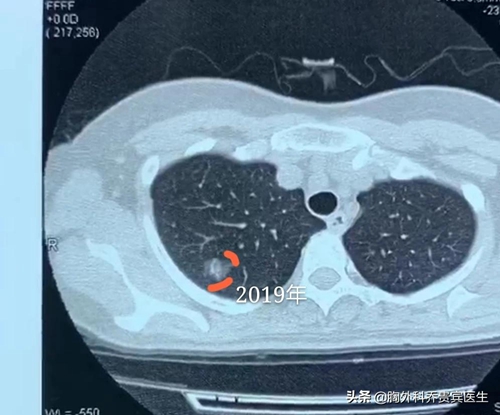

第三个方面,就是判断结节的生长速度。也就是说对于非常小的结节,如果小于8毫米或者6毫米,就需要复查。前后对比这个病灶生长的快慢,如果生长慢说明它是良性的,如果生长快就能提示它是恶性的。因此,对于这些小的病灶,一般来说医生都是建议进行随访观察的。